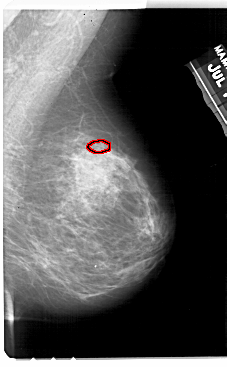

A_1944_1.LEFT_MLO

LEFT_MLO LINES 5491 PIXELS_PER_LINE 3406 BITS_PER_PIXEL 12 RESOLUTION 43.5 NON_OVERLAY

FILE: A_1944_1.RIGHT_MLO.OVERLAY

TOTAL_ABNORMALITIES 1

ABNORMALITY 1

LESION_TYPE CALCIFICATION TYPE PLEOMORPHIC DISTRIBUTION CLUSTERED

ASSESSMENT 4

SUBTLETY 3

PATHOLOGY BENIGN

TOTAL_OUTLINES 1

BOUNDARY